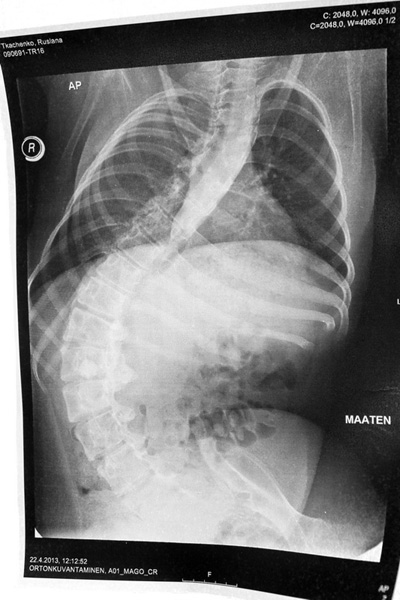

Рентгеновский снимок позвоночника: 1 стр 2 стр

Где-то, после пятого класса у меня начал развиваться сколиоз. Мышцы, к тому времени ослабли до такой степени, что уже не могли поддерживать позвоночник в ровном и правильном положении. К сожалению, врачи смогли мне только посоветовать одеть жесткий и ужасно неудобный корсет, от ношения которого долго болело всё тело.

В тот момент, когда я это сделала, пришло отчетливое понимание - пора менять свою жизнь. Ведь болезнь прогрессирует с каждым днем, заставляя мои мышцы всё больше слабеть. В данный момент у меня сильный сколиоз, который развивается, не щадя мои внутренние органы - и это основная проблема! Если с этим ничего не сделать, то уже через пару лет я не смогу дышать. Совсем. Позвоночник согнется до такой степени, что пережмет мои легкие. И это обрекает меня на мучительную… Надеюсь до этого не дойдет..

Свет надежды всё-таки есть! Полгода назад я узнала, что существует замечательная клиника в Хельсинки (Финляндия), которая проводит операции на позвоночнике уже много лет. Очень страшно было решиться на такой шаг, но я понимала, что другого шанса на жизнь у меня не будет. В апреле 2013-го я собрала лапки в лапки, прихватила родителей - и полетела прямиком в Ортон, на консультацию к настоящему светиле - доктору Дитриху. Этот хирург спас уже множество жизней. И после длительных обследований, он согласился спасти и мою.